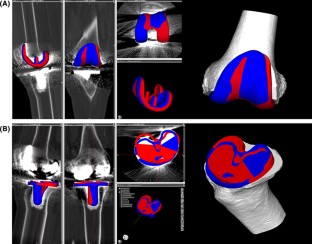

Consecutive 21 patients (30 knees) who underwent TKA using computed tomography (CT)-based PSI were retrospectively evaluated. Mean patient age was 69.2 years (62 to 77). The postoperative three-dimensional (3D) CT image were superimposed onto the preoperative 3D CT plan and measured the absolute difference in the prosthetic alignment using six parameters: coronal, sagittal, and axial alignment of the femoral and tibial prostheses. Cases in which the difference in the prosthetic alignment was greater than 3° were considered outliers.

For the femoral prosthesis, mean absolute differences between the preoperative 3D CT plan and postoperative 3D CT image were not significantly different and the rates of outliers were 10.0, 33.3, 23.3% in the coronal, sagittal, and axial planes. For the tibial prosthesis, mean absolute differences were significantly larger in the axial plane than in the coronal and sagittal planes (p < 0.001) and the rates of outliers were 23.3, 36.7, 63.3% in the coronal, sagittal, and axial planes. The rates of outliers for the axial alignment of tibial prosthesis were significantly higher than for the other five planes (p = 0.006).